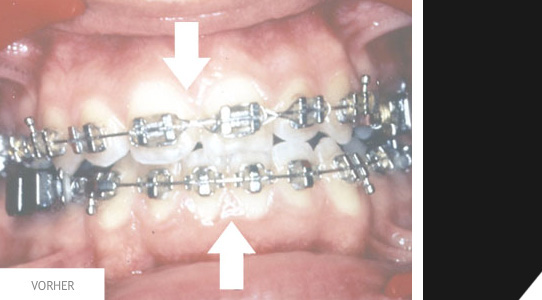

Hier noch ein Vorher- / Nachherfall, bei dem sogenannte Brackets eingesetzt werden.